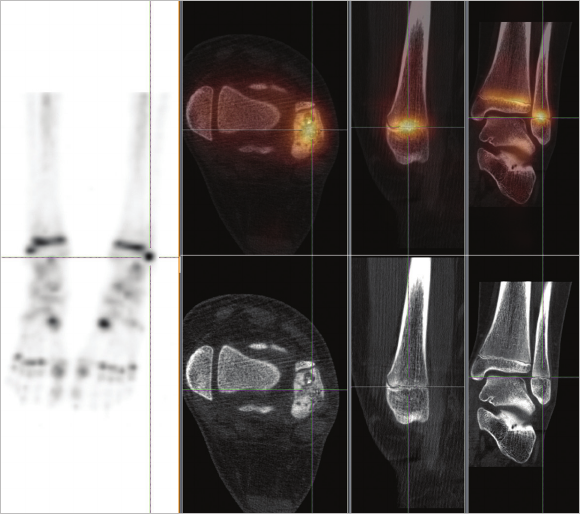

Figure 14 Tc-99m HDP SPECT/CT study of an 11-year-old female with anterolateral

pain on weight-bearing after fall with left ankle inversion. BrightView XCT exam reveals

low-grade left distal bula growth plate fracture and low-grade left talar head contusion.

Clinical data courtesy of Sutherland Nuclear Medicine, Sydney, Australia

Figure 15 Tc-99m HDP SPECT/CT study of a 43-year-old female patient with

right foot pain, status post trauma. BrightView XCT study was performed to

assess for possible fracture. SPECT images revealed multiple foci (at least three)

of activity within the mid-portion of the right foot that correlated to the joint

spaces on CT images. No evidence of fracture or activity correlated to bony

structures was observed.

Clinical data courtesy of Washington Hospital Center, Washington, DC